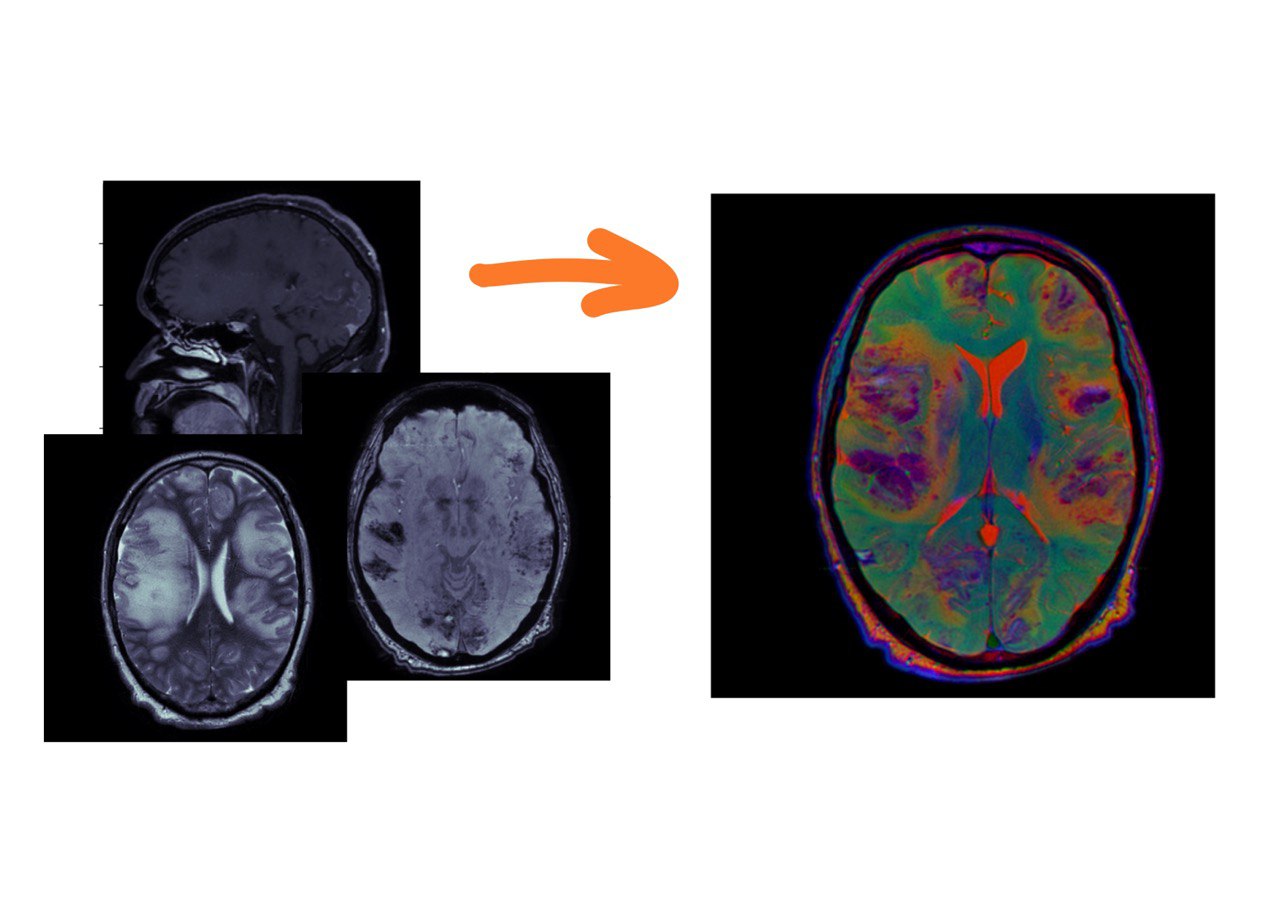

Каждая из этих серий содержит полезную информацию, и мы хотим показывать нейросетке все три взвешенности. Для этого их нужно подавать как каналы (примерно так, как делал фотографии Прокудин-Горский в начале 20 века: делал три фотографии через разные светофильтры, а потом накладывал их друг на друга).

Прокудин-Горский

Понятно, что для этого серии должны быть ориентированы идентичным образом. Сейчас покажу, как это можно сделать.

%%time

filenamesDICOM = reader.GetGDCMSeriesFileNames('T1_CE')

reader.SetFileNames(filenamesDICOM)

t1_sitk = reader.Execute()

filenamesDICOM = reader.GetGDCMSeriesFileNames('SWI')

swi_sitk = reader.Execute()

filenamesDICOM = reader.GetGDCMSeriesFileNames('T2')

t2_sitk = reader.Execute()

swi_resampled = resample(swi_sitk, t2_sitk)

t1_resampled = resample(t1_sitk, t2_sitk)

t2_sitk_array = normalize(sitk.GetArrayFromImage(t2_sitk))

swi_resampled_array = normalize(sitk.GetArrayFromImage(swi_resampled))

t1_resampled_array = normalize(sitk.GetArrayFromImage(t1_resampled))

stacked = np.stack([t2_sitk_array, swi_resampled_array, t1_resampled_array,])

to_rgb = stacked[:,t2_sitk_array.shape[0]//2,:,:].transpose(1,2,0)

im = Image.fromarray((to_rgb * 255).astype(np.uint8))

im

>>CPU times: total: 5.02 s

Wall time: 3.52 s

final